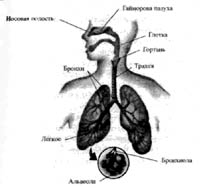

Гайморовы пазухи, глотка, гортань, внеторакальные (расположенные выше грудной клетки) участки трахеи и так далее, передающие поток воздуха из окружающей среды вниз к альвеолам через дыхательные ворота организма, а также нос и рот, определяются как дыхательные пути (рис. 3). В процессе спонтанного дыхания дыхательные пути активно расширяются при вдыхании и сокращаются при выдыхании соответственно расширению или сужению внутреннего диаметра дыхательного пути. В результате этого на интенсивность воздушного потока существенно влияет даже небольшое уменьшение внутренних диаметров дыхательных путей, что значительно увеличивает их сопротивление. Это сопротивление проистекает из психологических расстройств или всякого рода внешних воздействий, нежелательных или желательных (в некоторых процессах пранаямы), что приводит к вентиляционному расстройству.

Рис. 3. Анатомия дыхательной системы

Жизненно важной частью респираторного тракта являются верхние дыхательные пути. Нос с носовой раковиной, рот, глотка с гортанью и часть трахеи составляют верхние дыхательные пути. Здесь нас будет интересовать в основном роль носа и рта в дыхательном процессе.

Нос, с его слизистыми оболочками, рецепторами, нервными ответвлениями и носовой раковиной, превосходно сконструирован природой для осуществления первичных дыхательных функции. Вдыхаемый носом воздух подвергается существенным изменениям, а именно увлажняется и разогревается при прохождении через носовую раковину благодаря ее вихревой функции (у нее неровная поверхность). Пыль и другие частицы прилипают к слизистой носа, когда носовая раковина втягивает воздух. Это сводит к минимуму раздражение и дыхательные инфекции и позволяет различать качества запахов, а также защищает дыхательные пути от возможных повреждений. Дыхание через нос обладает существенными преимуществами. Дыхание через рот принимает на себя вторичную дыхательную функцию, когда потребность в воздухе не может удовлетворяться через нос, например, при экстремальных атлетических упражнениях или в случае респираторных заболеваний, если носовые пазухи заполнены гноем. В подобных случаях дыхательные мускулы автоматически заставляют переключаться с носового дыхания на ротовое.

Когда мы дышим ртом, пропускная способность дыхания соответственно подвергается негативному воздействию, поскольку ротовой проход шире носового и отсутствие носовой перегородки приводит к несообразному сопротивлению воздуха. Степень негативного воздействия зависит от различного положения челюстей, языка, губ и неба. Когда дыхание через рот становится регулярным, нежелательные проблемы возникают в таких областях, как шея и нос.

Естественно также, что воздушный поток не всегда попадает одновременно в обе ноздри, он периодически изменяет свою траекторию движения с одной ноздри на другую. Такое чередование происходит с интервалом около 2 или 3 часов, что вы и сами можете время от времени самостоятельно наблюдать. Причинами такого чередования могут бьпъ различные психологические или физические воздействия или влияние окружающей среды.

Сведения об особенностях дыхания через нос и рот позволяют использовать в пранаяме специальные техники для регулирования интенсивности и характера воздушного потока (в основном через ноздрю). Руководство такой дыхательной техникой требует сосредоточенности и пристального внимания.